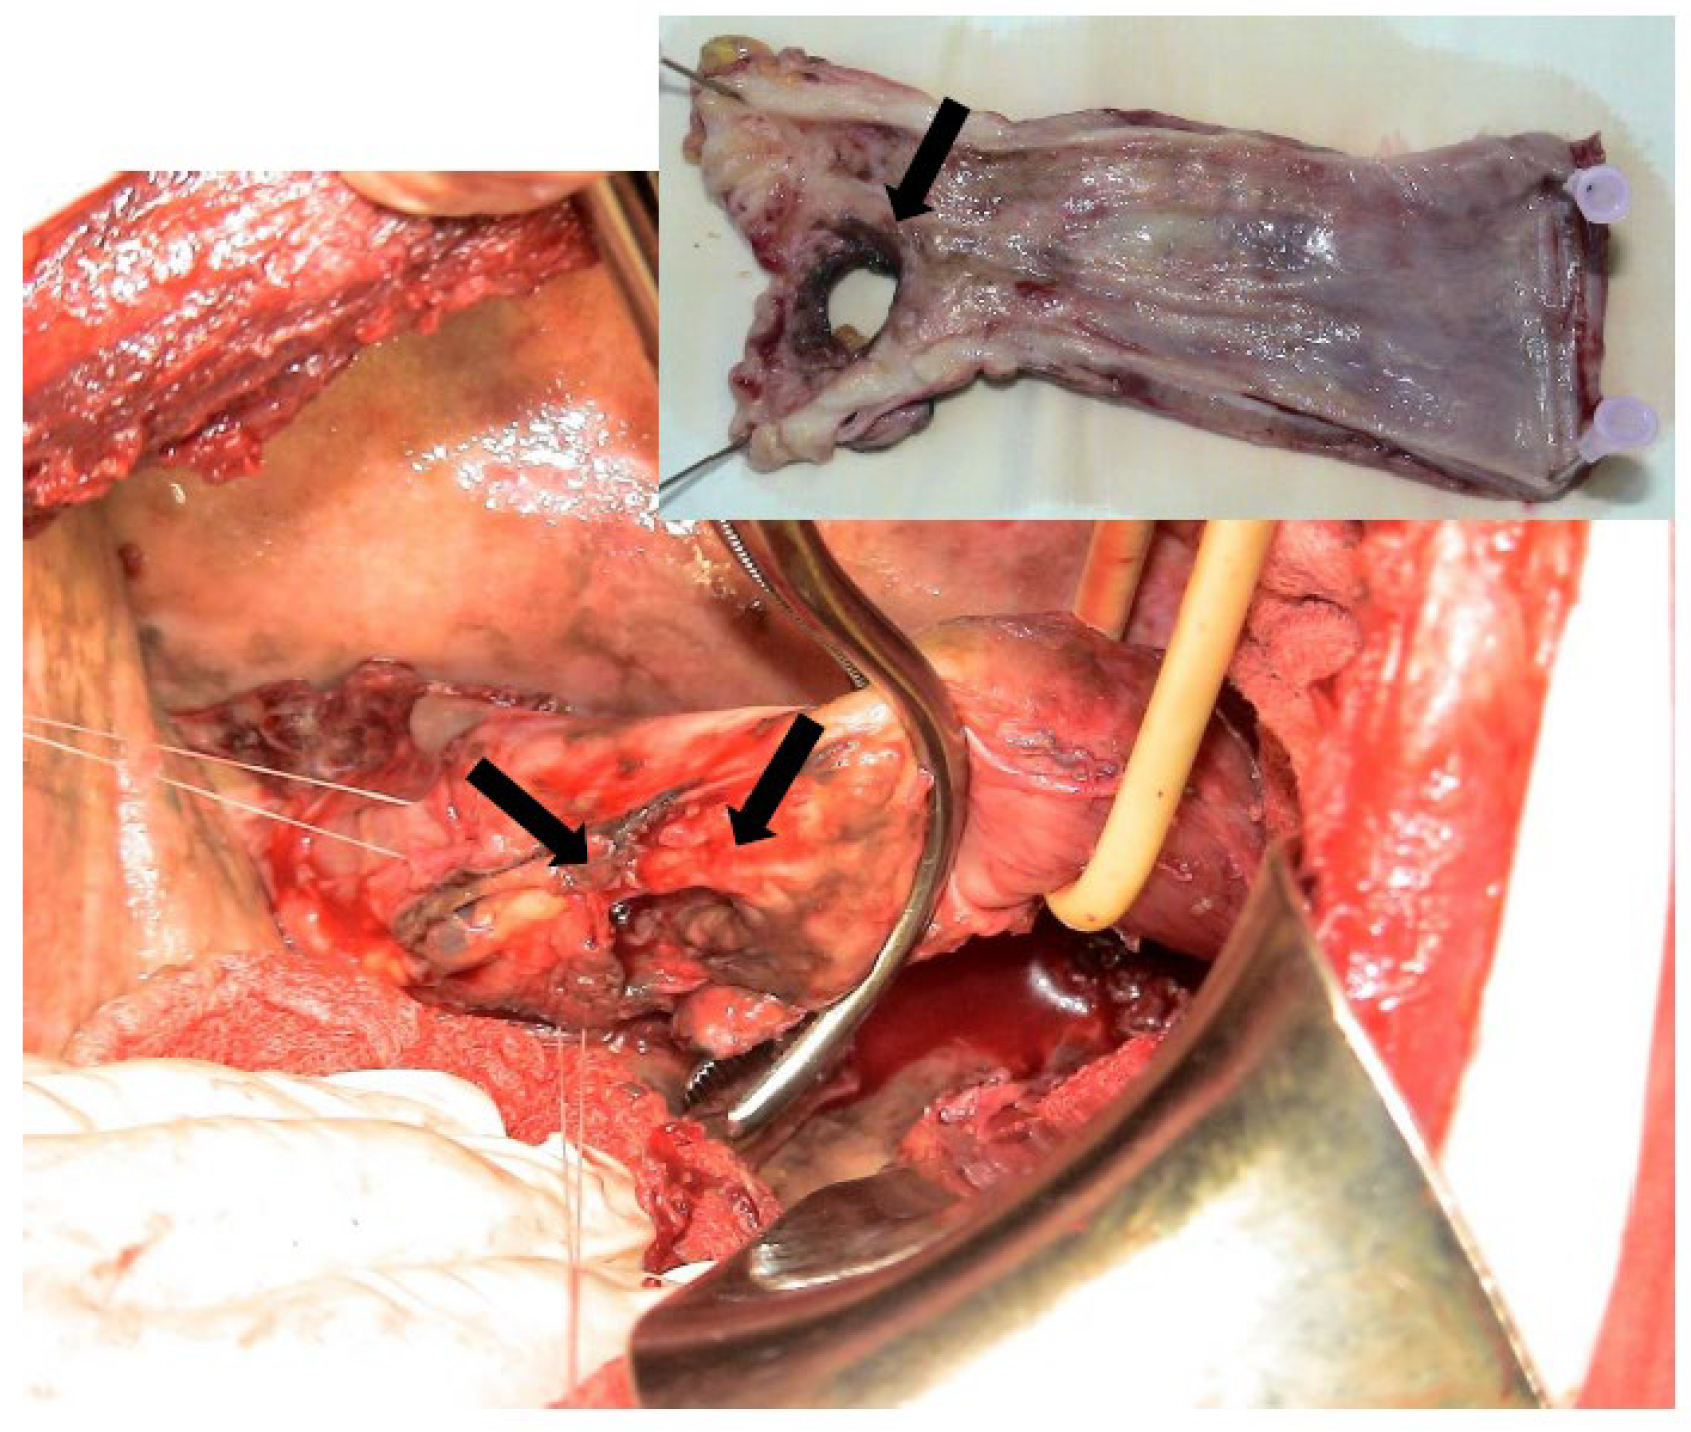

10. Surgical Management

Esophageal Diversion (Exclusion)

- Sulpice, L.; Dileon, S.; Rayar, M.; Badic, B.; Boudjema, K.; Bail, J.; Meunier, B. Conservative surgical management of Boerhaave’s syndrome: Experience of two tertiary referral centers. Int. J. Surg. 2013, 11, 64–67. [Google Scholar] [CrossRef]

- Brinster, C.J.; Singhal, S.; Lee, L.; Marshall, M.B.; Kaiser, L.R.; Kucharczuk, J.C. Evolving options in the management of esophageal perforation. Ann. Thorac. Surg. 2004, 77, 1475–1483. [Google Scholar] [CrossRef]

- Yan, X.L.; Jing, L.; Guo, L.J.; Huo, Y.K.; Zhang, Y.C.; Yan, X.W.; Deng, Y.Z. Surgical management of Boerhaave’s syndrome with early and delayed diagnosis in adults: A retrospective study of 88 patients. Rev. Esp. Enferm. Dig. 2020, 112, 669–674. [Google Scholar] [CrossRef] [PubMed]

- Mathisen, D.J.; Grillo, H.C.; Vlahakes, G.J.; Dagget, W.M. The omentum in the management of complicated cardiothoracic problems. J. Thorac. Cardiovasc. Surg. 1988, 95, 677–684. [Google Scholar] [CrossRef]

- Sakamoto, Y.; Tanaka, N.; Furuya, T.; Ueno, T.; Okamoto, H.; Nagai, M.; Murakawa, T.; Takayama, T.; Mafune, K.; Makuuchi, M.; et al. Surgical management of late esophageal perforation. Thorac. Cardiovasc. Surg. 1997, 45, 269–272. [Google Scholar] [CrossRef] [PubMed]

- Kotsis, L.; Kostic, S.; Zubovitis, K. Multimodality treatment of esophageal disruptions. Chest 1997, 112, 1304–1309. [Google Scholar] [CrossRef]

- Okamoto, H.; Onodera, K.; Kamba, R.; Taniyama, Y.; Sakurai, T.; Heishi, T.; Teshima, J.; Hikage, M.; Sato, C.; Maruyama, S.; et al. Treatment of spontaneous esophageal rupture (Boerhaave’ syndrome) using thoracoscopic surgery and sivelestat sodium hydrate. J. Thorac. Dis. 2018, 10, 2206–2212. [Google Scholar] [CrossRef] [PubMed]

- Kollmar, O.; Lindemann, W.; Richter, S.; Steffen, I.; Pistorius, G.; Schilling, M.K. Boerhaave’s syndrome: Primary repair vs. esophageal resection–case reports and metaanalysis of the literature. J. Gastrointest. Surg. 2003, 7, 726–734. [Google Scholar] [CrossRef] [PubMed]

- Haveman, J.W.; Nieuwenhuijs, V.B.; Kobold, J.P.M.; van Dam, G.M.; Plukker, J.T.; Hofker, H.S. Adequate debridement and drainage of the mediastinum using open thoracotomy or video-assisted thoracoscopic surgery for Boerhaave’s syndrome. Surg. Endosc. 2011, 25, 2492–2497. [Google Scholar] [CrossRef] [PubMed]

- Ariza-Traslaviña, J.; Caballero-Otálora, N.; Polanía-Sandoval, C.A.; Perez-Rivera, C.J.; Tellez, L.J.; Mosquera, M. Two-staged surgical management for complicated Boerhaave syndrome with esophagectomy and deferred gastroplasty: A case report. Int. J. Surg. Case Rep. 2023, 103, 107881. [Google Scholar] [CrossRef] [PubMed] [PubMed Central]

- Matthews, H.R.; Mitchell, I.M.; McGuigan, J.A. Emergency subtotal oesophagectomy. Br. J. Surg. 1989, 76, 918–920. [Google Scholar] [CrossRef]

- Elliott, J.A.; Buckley, L.; Albagir, M.; Athanasiou, A.; Murphy, T.J. Minimally invasive surgical management of spontaneous esophageal perforation (Boerhaave’s syndrome). Surg. Endosc. 2019, 33, 3494–3502. [Google Scholar] [CrossRef]